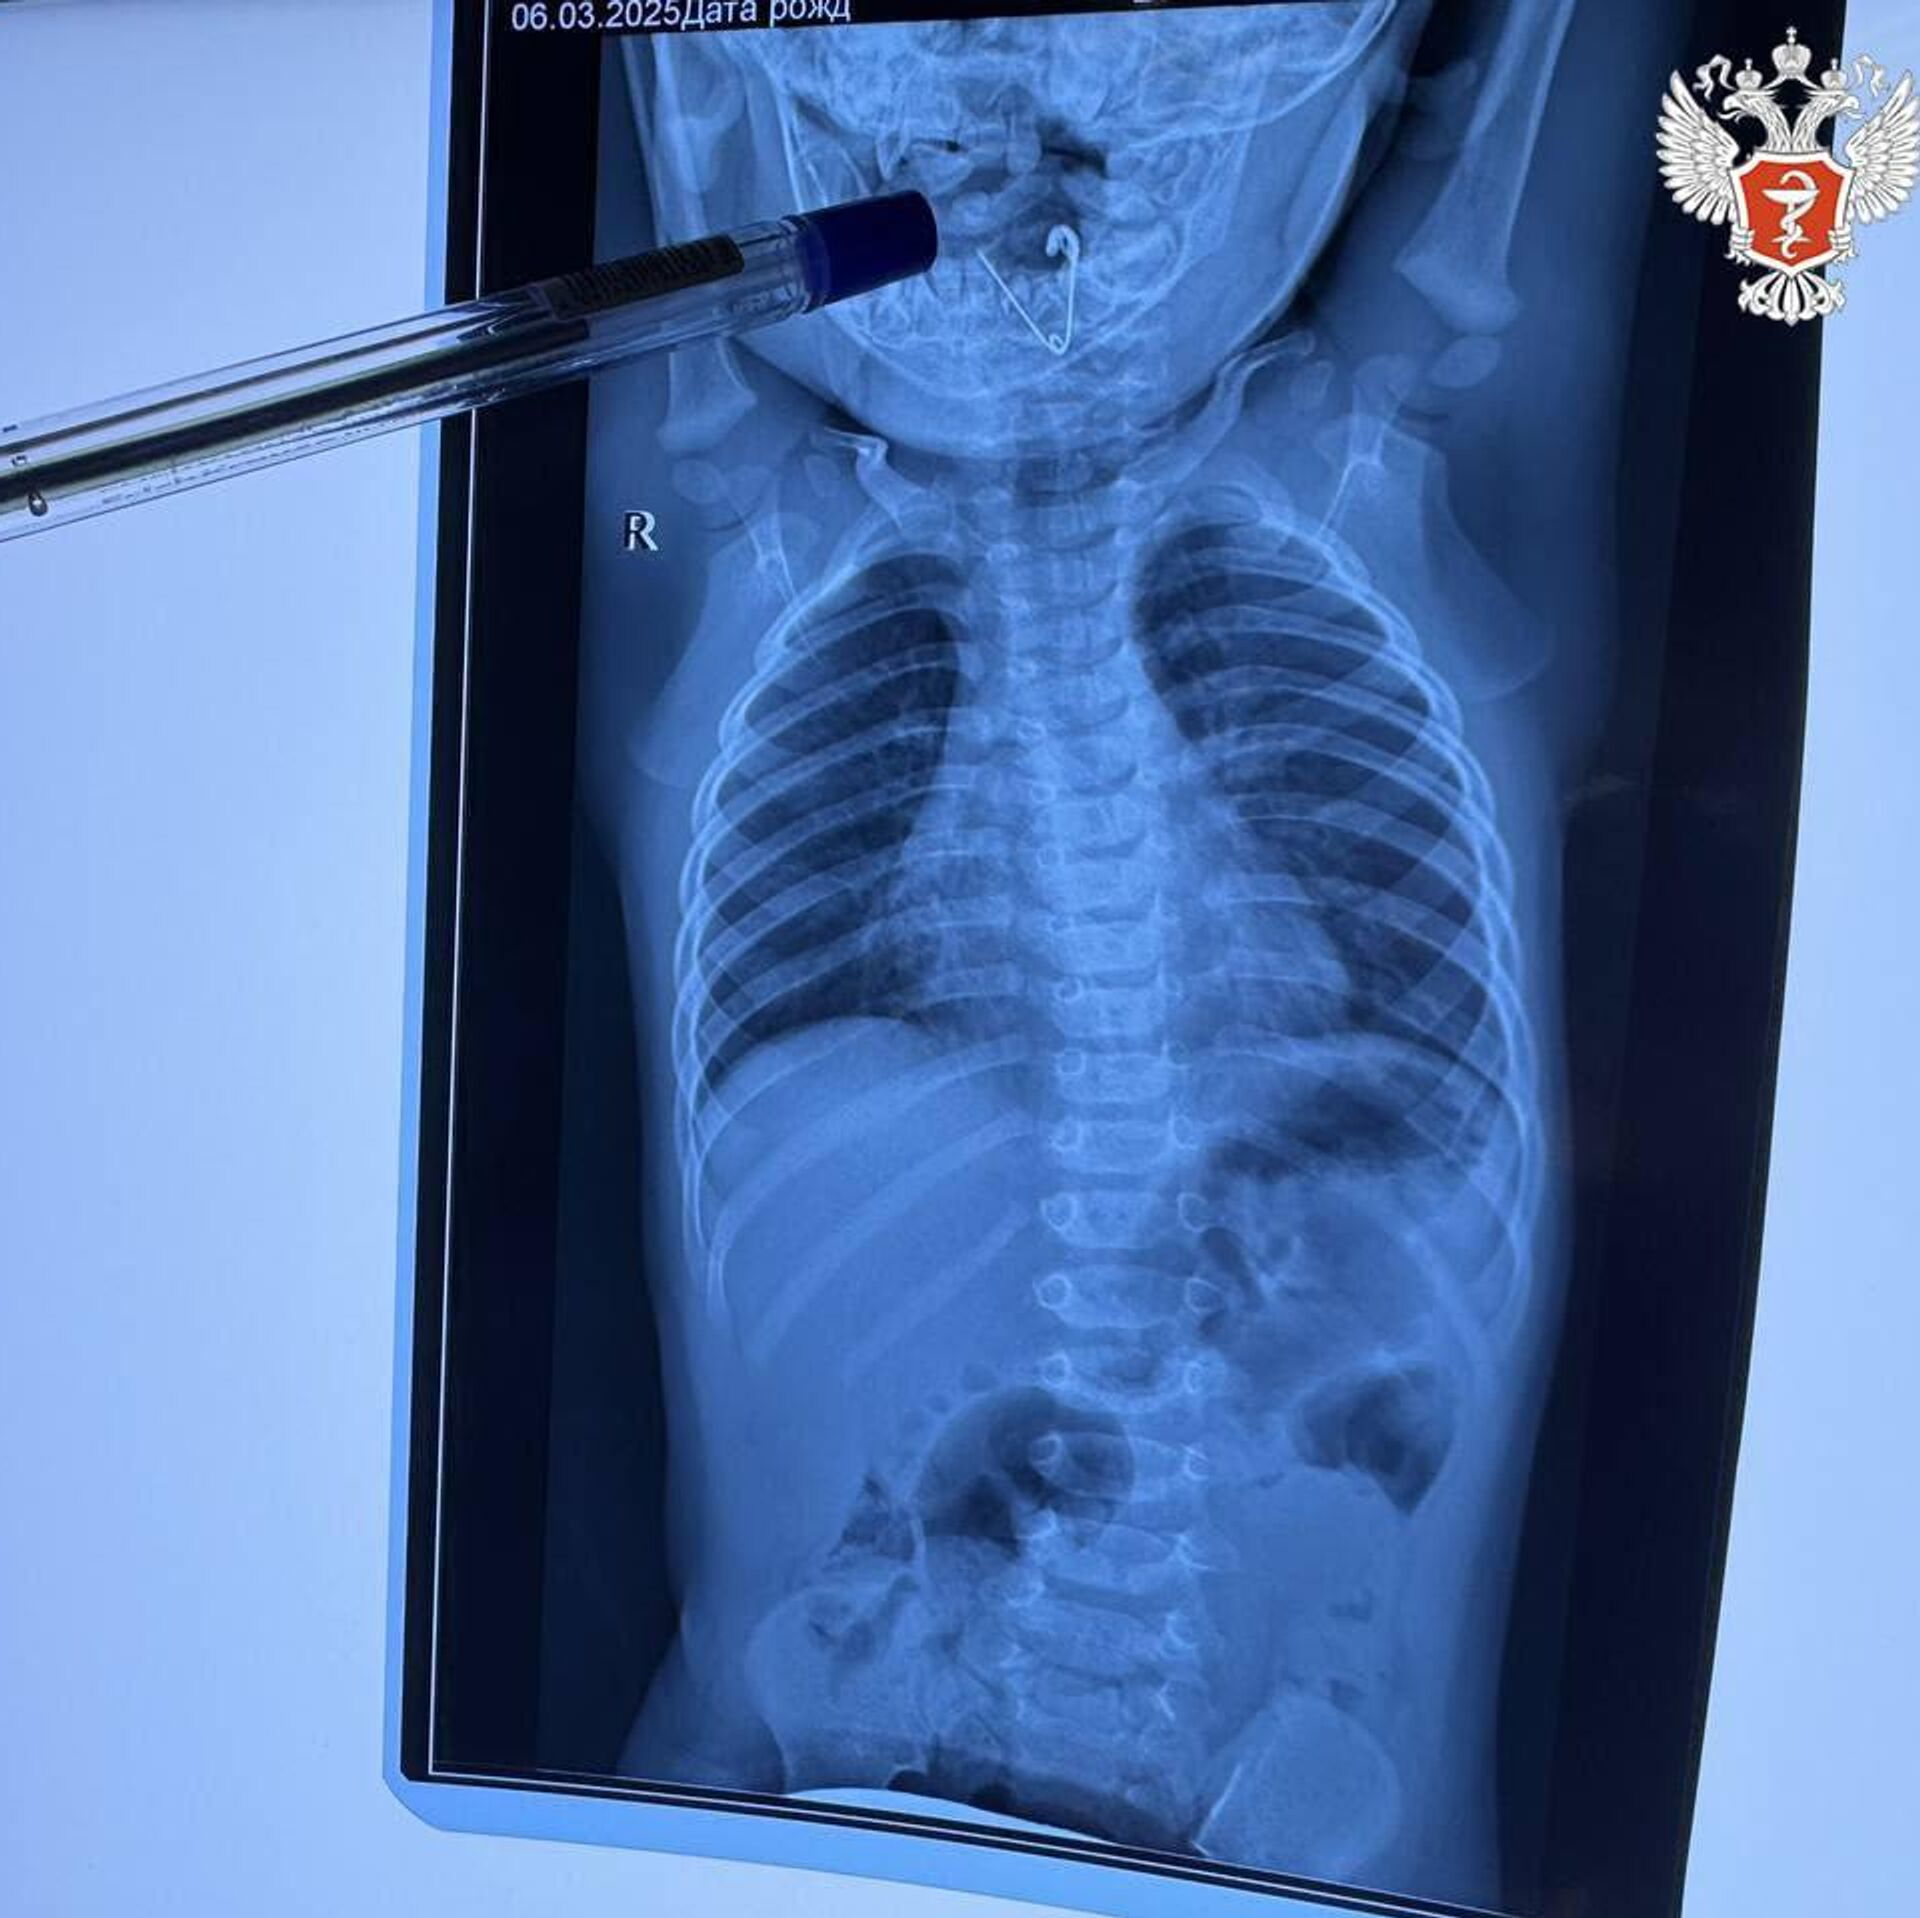

"Бригада медиков госпитализировала маленького пациента в приемное отделение Черниговской центральной районной больницы. Специалисты выполнили обзорную рентгенографию органов грудной клетки и в пищеводе обнаружили тень инородного тела. После этого ребенка оперативно ребенка доставили в Краевую детскую клиническую больницу №1 г. Владивостока", – сказано в сообщении.

При повторном рентген-обследовании врачи увидели открытую булавку и удалили ее при помощи щипцов под контролем эндоскопической техники, уточнили в Минздраве. Сейчас ребенок чувствует себя хорошо, скоро его выпишут домой, добавили в пресс-службе.